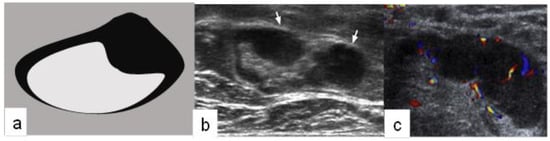

- Ecanow, J.; Abe, H.; Newstead, G.M.; Ecanow, D.B.; Jeske, J.M. Axillary Staging of Breast Cancer: What the Radiologist Should Know. Radiographics 2013, 33, 1589–1612. [Google Scholar] [CrossRef]